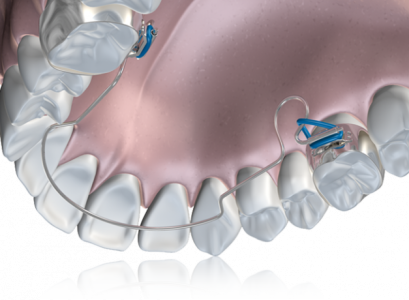

Лингвальная дуга — это ортодонтический аппарат, используемый для выравнивания зубов, расположенных на нижней челюсти. Представляет собой проволоку, изготовленную из стали, платины или золота, которая изгибается по язычной стороне зубов и присоединяется специальными опорными кольцами к первым молярам нижней челюсти. Преимуществом лингвальной дуги является её доступная стоимость, однако, она может справляться лишь с некоторыми патологиями прикуса, такими как незначительное расширение челюсти, щели между зубами, повышенная скученность зубов, искривление зубов в ряду. Чаще применяется в детской стоматологии, чем у взрослых.